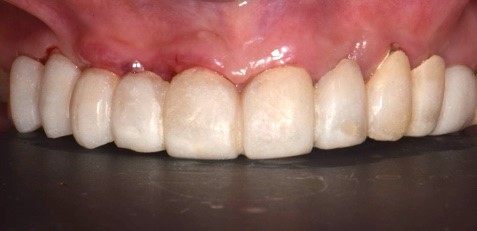

Protesi finale

Fig. 6(a)

Protesi finale 2

Fig. 6(b) Protesi finale.

I restauri si adattavano perfettamente, poiché il design dell'abutment iPhysio® aveva modellato i tessuti molli in modo così predicibile da poter essere riprodotto digitalmente sul profilo di emergenza della protesi finale (Fig. 7 a,b,c,d,e,f).